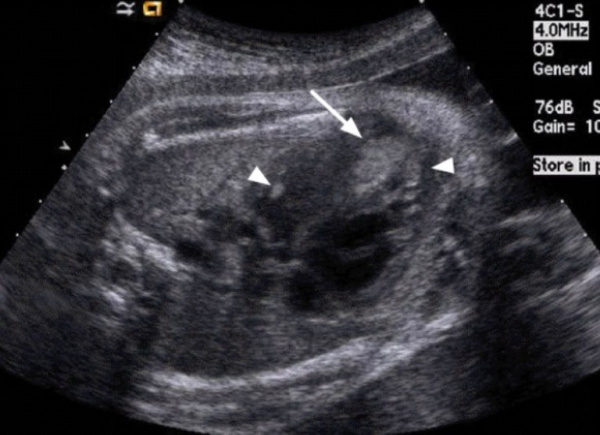

Рис. 1. Эхокардиограмма ребенка (девочки) с рабдомиомой. Крупный узел рабдомиомы в межжелудочковой перегородке (1) и менее крупные узлы в задней стенке левого желудочка (2). Эхоплотность образований выше, чем миокарда.

Рис. 2. Эхокардиограмма матери этого же ребенка. В межжелудочковой перегородке несколько эхоплотных образований (стрелки).

Рабдомиома сердца эхографически выглядят как достаточно четко очерченные образования. Чаще всего располагаются в миокарде левого желудочка, реже – в правом, еще реже – в предсердиях, кавоатриальных и атриовентрикулярных соединениях, эпикарде. Метастазирование не типично [8]. Наличие двух и более рабдомиом четко коррелирует с туберозным склерозом, одиночные рабдомиомы сердца такой связи, как правило, не имеют. По нашему опыту (18 пациентов), чем меньше объем новообразования, тем выше акустическая плотность, приближающаяся к эталонной эхоплотности (эндо-, эпи- и перикард). Эхоплотность больших рабдомиом практически не отличается от эхоплотности миокарда. В толще новообразования выявляются мелкие эхонегативные очажки (области некрозов) и эхопозитивные очажки (отложения кальция) (рис. 3).

Рис. 3. Эхокардиограмма гигантской рабдомиомы (стрелка) у девочки марфаноидного статуса без признаков туберозного склероза (субксифоидальный доступ).